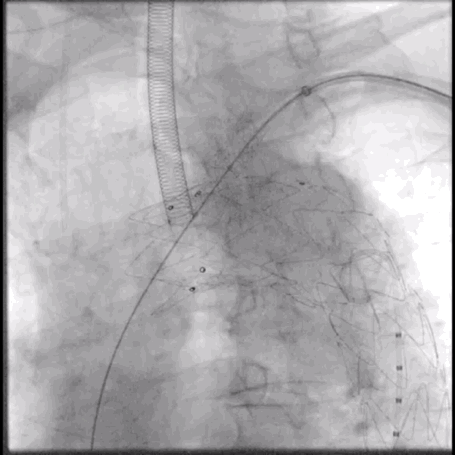

5. 经左肱动脉导入VBX(10mm*39mm)至开窗口释放,并使用10mm*20mm Mustang球囊行支架内扩张。

泥鳅导丝怎么用符伟国/王利新教授团队:0.035"普通泥鳅导丝进行胸主动脉弓上分支原位开窗的病例分享_https://www.jmylbn.com_新闻资讯_第19张

确认LSA及椎动脉开口位置

泥鳅导丝怎么用符伟国/王利新教授团队:0.035"普通泥鳅导丝进行胸主动脉弓上分支原位开窗的病例分享_https://www.jmylbn.com_新闻资讯_第20张

释放10mm*39mm VBX球扩支架

泥鳅导丝怎么用符伟国/王利新教授团队:0.035"普通泥鳅导丝进行胸主动脉弓上分支原位开窗的病例分享_https://www.jmylbn.com_新闻资讯_第21张

使用10mm*20mm球囊扩张分支支架

泥鳅导丝怎么用符伟国/王利新教授团队:0.035"普通泥鳅导丝进行胸主动脉弓上分支原位开窗的病例分享_https://www.jmylbn.com_新闻资讯_第22张

RAO位置造影大支架封闭良好,无内漏

泥鳅导丝怎么用符伟国/王利新教授团队:0.035"普通泥鳅导丝进行胸主动脉弓上分支原位开窗的病例分享_https://www.jmylbn.com_新闻资讯_第23张

LAO位置造影左锥动脉血流良好

6. 最终造影:主动脉弓部瘤病变显影消失,主体支架形态良好,分支支架通畅,左椎动脉显影良好。